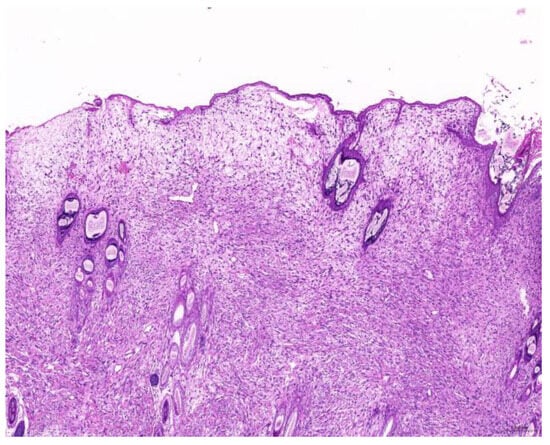

Of the 85 biopsy samples, the most commonly affected system was the integumentary system (48.2%, 41/85), followed by the reproductive system (42.4%, 36/85), the digestive system (8.2%, 7/85), and the urinary system (1.2%, 1/85) (Table 3). Of the 41 rabbits with an affected integumentary system, 39 had neoplastic and two had non-neoplastic disorders. The median age of these affected rabbits was 87 (12–149) months. There were 15 females and 26 males, with a female-to-male ratio of 0.54:1. The most common integumentary diagnosis was fibrosarcoma (29.3%, 12/41) (Figure 1), followed by trichoblastoma (19.5%, 8/41) (Figure 2), fibroma (9.8%, 4/41) (Figure 3), lipoma (7.3%, 3/41), mammary gland adenoma (7.3%, 3/41), and mammary gland adenocarcinoma (4.9%, 2/41) (Figure 4), among others. The median age of the rabbits with fibrosarcomas was 108 (54–126) months. Of the 12 cases with fibrosarcoma, 4 were females and 8 were males, with a female-to-male ratio of 0.5:1. The tumors were located on the neck, chest, abdomen, and extremities. The median age of the rabbits with fibromas was 101 (48–108) months. All four of these were males, with tumors exclusively located on the chest. Myxosarcoma was diagnosed in a 108-month-old male rabbit, with the tumor located on the left elbow (Figure 5).

Figure 1. Fibrosarcoma. The neoplasm is located in the dermis and is arranged in streams (scale bar = 200 µm). Hematoxylin and eosin staining.